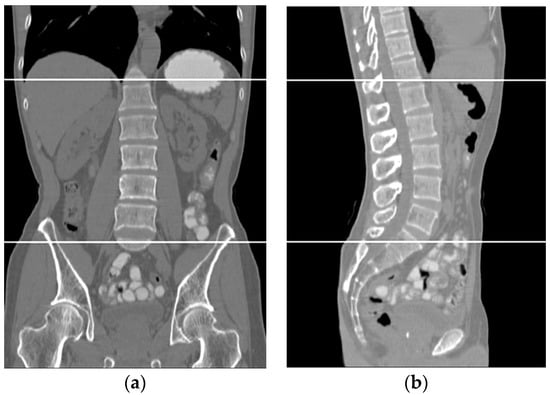

Figure 11 shows side and front views for two subjects where the liver is bounded by black contours.

Figure 11. Two samples of the results of the liver segmentation method. (a) Front view, (b) side view.